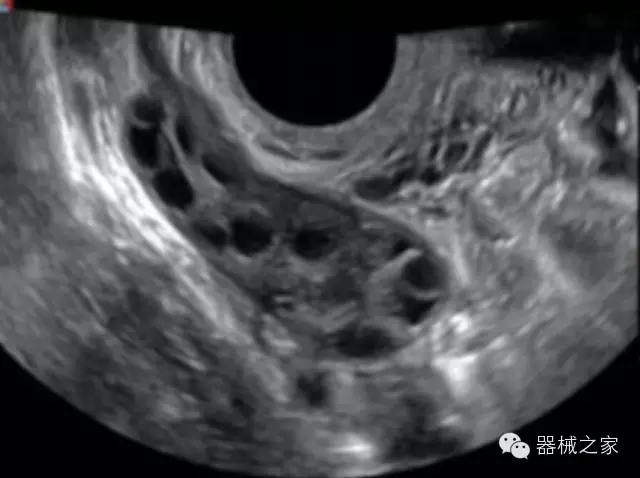

經(jīng)典產(chǎn)品:S8EXP

臨床圖片賞析

產(chǎn)品特點(diǎn)

優(yōu)異的成像技術(shù)

·亞陣元技術(shù):獨(dú)有的亞陣元技術(shù),對獨(dú)立晶片做二次切割,減少旁瓣偽像,增加臨床診斷的準(zhǔn)確性;

·μ-Scan微米成像技術(shù):開立獨(dú)有的μ-Scan技術(shù),還原出真實(shí)細(xì)膩、層次對比優(yōu)異的二維圖像;

·倒相諧波成像技術(shù):倒相諧波技術(shù)在去除基波信號的基礎(chǔ)上獲取兩倍二次諧波信號,提高組織圖像的對比分辨力;

·智能微血流成像技術(shù):智能微血流捕捉技術(shù)可以提取出隱藏在背景噪聲中的弱血流信號,大大提高低速血流的敏感性;

全面的臨床解決方案

超聲科常規(guī)領(lǐng)域應(yīng)用

·移植S40高端臺式彩超高端平臺技術(shù),滿足超聲科腹部、淺表、婦產(chǎn)科、心血管、肌骨等應(yīng)用,提供超聲科完美解決方案;

·實(shí)時的彈性成像技術(shù):提高了小器管(乳腺,甲狀腺、淺表軟組織腫瘤等)疾病鑒別診斷;

·IMT血管內(nèi)中膜自動測量:為血管性疾病評估提供了有效的評估手段;

·心功能綜合指數(shù)(TEI指數(shù)):用于左、右心室整體心臟收縮舒張功能評估的測量方法;

·全方位可調(diào)M型:有利于更好的觀察心腔大小及室壁階段性運(yùn)動的異常情況;

·組織多普勒成像(TDI):TDI可定量評價心肌運(yùn)動,判斷是否有局部病變,還可評價早期的舒張功能;

·高效3D/4D成像技術(shù):高速的4D幀頻,豐富的3D成像模式,智能斷層切片功能;

POC領(lǐng)域解決方案

·外觀小巧;

·穿刺增強(qiáng)技術(shù):可有效提高進(jìn)針區(qū)圖像分辨率,提高進(jìn)針亮度,全面提高一次性穿刺的成功率;

全面的術(shù)中探頭解決方案

·小凸探頭:開放性手術(shù),實(shí)時監(jiān)測病灶位置,提高手術(shù)成功率,可應(yīng)用于麻醉科、肝膽外科、腫瘤外科、神經(jīng)外科、泌尿外科等手術(shù);

·L型線陣探頭:高分辨率圖像,清晰顯示病灶位置,提高手術(shù)成功率,可應(yīng)用于麻醉科、胸外科、肝膽外科、腫瘤外科、神經(jīng)外科、泌尿外科等應(yīng)用;

·MPTEE:經(jīng)食道探頭術(shù)中監(jiān)測,可測量心臟前負(fù)荷(左室舒張末期大小、右房大?。?、心排血量、后負(fù)荷、收縮功能、室壁運(yùn)動分析、肝靜脈血流(與中心靜脈壓相關(guān))等,術(shù)后還能及時評估手術(shù)效果評估;

·獨(dú)有的大角度及實(shí)時溫控技術(shù),能同一切面顯示宮頸及宮體,有效減低了患者的痛苦,及保護(hù)粘膜保證了醫(yī)療安全;

高效的人機(jī)工程學(xué)設(shè)計(jì)

·15‘’高清醫(yī)用顯示器;

·內(nèi)置雙探頭接口;

·可升降臺車,1拖3探頭擴(kuò)展器;

·m-Tuning一鍵優(yōu)化;

CFDA注冊證編號

·粵食藥監(jiān)械(準(zhǔn))字20132230491